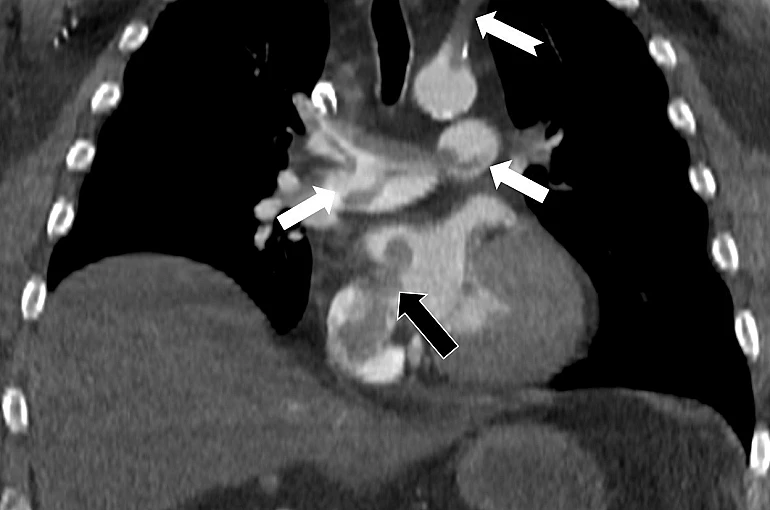

Bir dönem Özel Denizli Tekden Hastanesi’nde de görev yapan Prof. Dr. Nevzat Karabulut’un yaptığı çalışmada; akciğerin bilgisayarlı tomografi anjiyografisi sayesinde toplar damarlardan kaynaklanan pıhtının akciğer damarlarını tıkaması yanında, kalpteki delik nedeniyle kalbin sağ tarafından sol tarafına geçerek ana atardamara ulaştığı ve sol kol damarını tıkadığı gösterildi.

Emboli görüntülemesi konusunda çok sayıda bilimsel çalışması bulunan Prof. Dr. Karabulut, genelde bacak damarlarından kaynaklanan pıhtıların ölümcül olabilen akciğer embolisine yol açması yanında, kalp deliği olan hastalarda ana atardamar yoluyla beyin, kol ve bacak gibi vücudun diğer bölgelerine de geçerek ani damar tıkanmasına (paradoks emboli) bağlı bulgulara yol açtığını belirtti. Prof. Dr. Karabulut’un çalışmasında nedeni bilinmeyen pıhtı atmalarında kalpteki gizli deliklerin mutlaka araştırılması gerektiği vurgulanarak ekokardiyografi ve bilgisayarlı tomografi tetkiklerinin erken ve doğru tanı koymada hayat kurtarıcı rolüne dikkat çekildi.